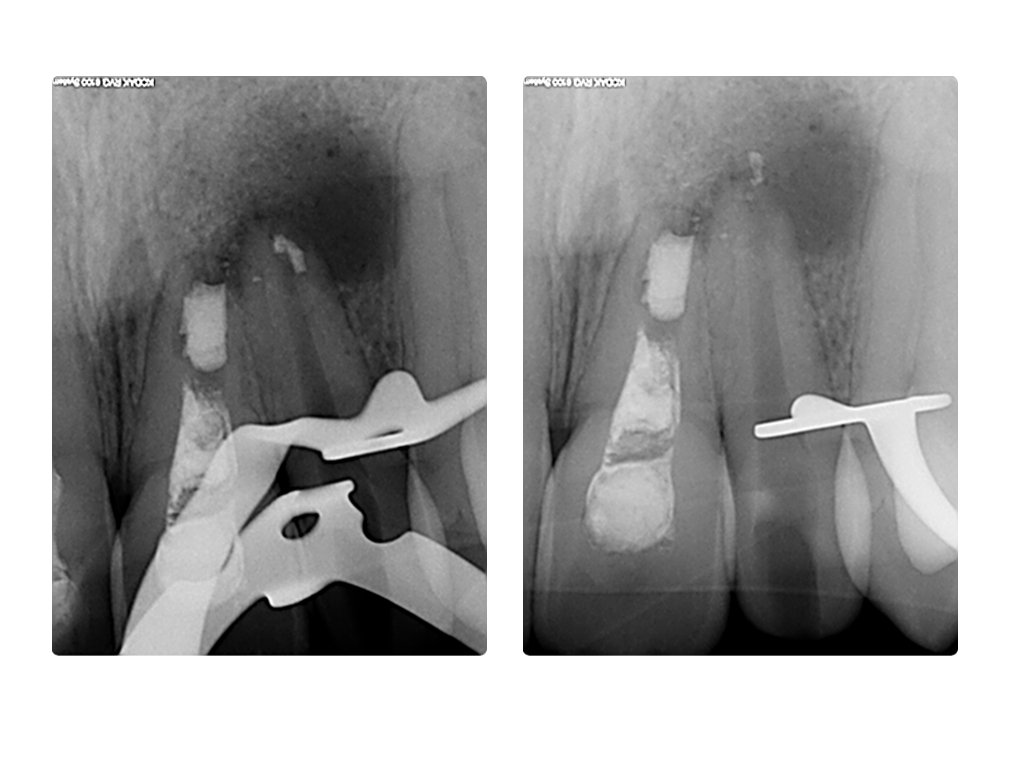

ws7.007 Veröffentlicht 27. Juni 2014 am 1024 × 768 in Einbahnstraße WSR (2) WF und retrograde WF Entfernung 22